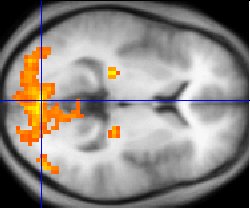

- fMRI

fMRI or functional magnetic resonance imaging is a technique frequently applied to human subjects, in which changes in cerebral blood flow can be detected in an MRI apparatus and are taken to indicate relative activity of larger scale brain regions (on the order of hundreds of thousands of neurons).